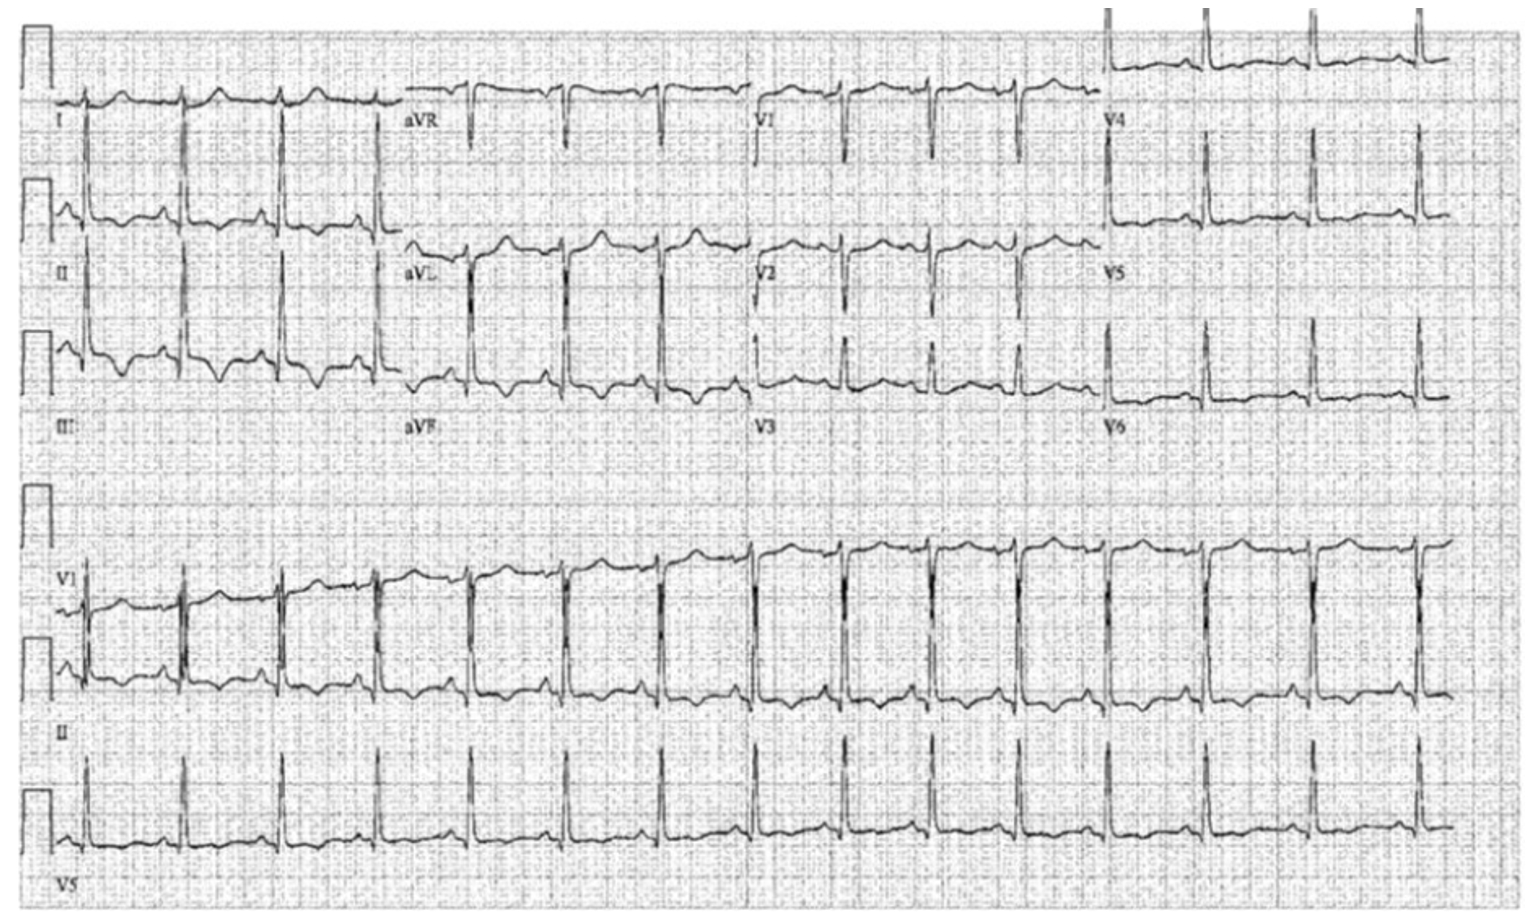

A diagnosis of inferior ST-elevation myocardial infarction was made. She was treated with oral aspirin and prasugrel load as well as intravenous heparin and taken urgently to the catheterization laboratory. Diagnostic coronary angiography was significant for single vessel coronary artery disease (CAD) of the right coronary artery (RCA), with acute complete occlusion of the mid-RCA (Figure 2A-B). She was treated successfully with primary percutaneous coronary intervention and implant of two overlapping drug eluting stents in the mid-RCA (Figure 2C).